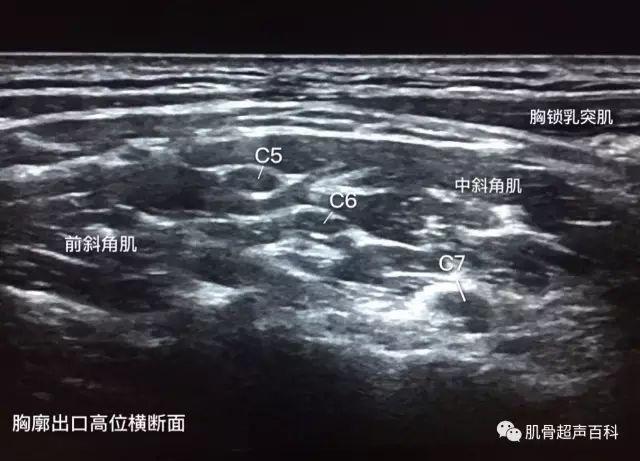

超声下臂丛神经的真面目(臂丛神经阻滞秘籍)

臂丛神经